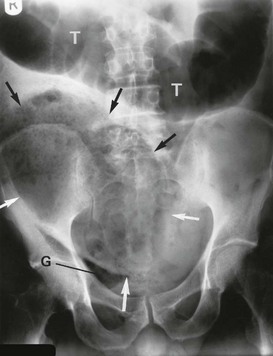

Perforation is essentially a clinical diagnosis but can be confirmed by the presence of free gas in the peritoneal cavity on plain radiography (or CT scan). This is visible as a radiolucent line beneath the hemidiaphragms on an erect chest film (see Fig. 19.8) or a lateral decubitus abdominal film. Note that CT scanning is more sensitive than plain films for detecting small quantities of free gas. Free gas is rare in perforated appendicitis or perforated gall bladder. If imaging fails to support the clinical findings, action should be based on the clinical diagnosis.